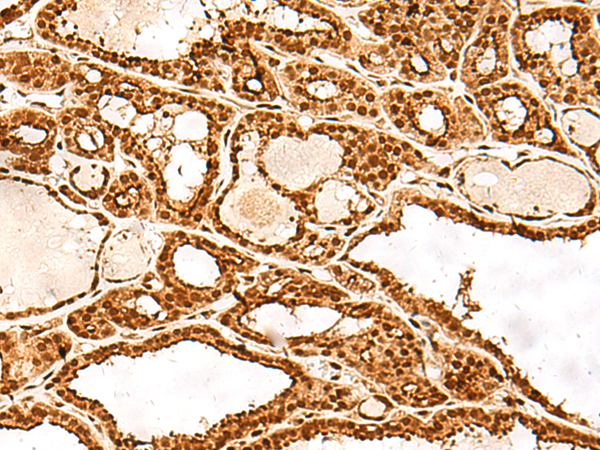

IHC positive control: |

Human tonsil and Human thyroid cancer |